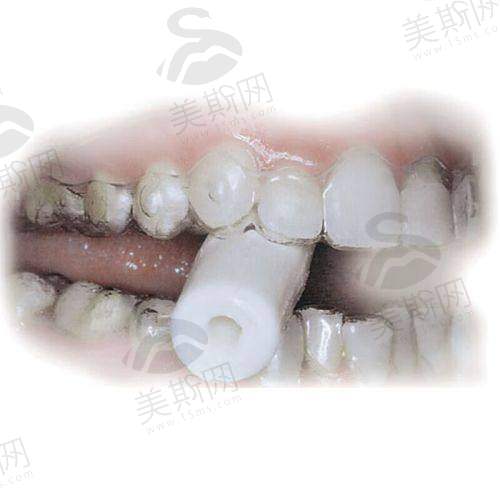

4. 美学修复:全瓷牙冠(色泽自然,媲美真牙)、瓷贴面(微创改善牙齿着色、间隙),适合前牙美观修复;

种植牙技术:采用3D数字化种植系统,术前通过CBCT扫描获取牙槽骨三维数据,结合3D导板精细定位种植体角度与深度,实现“毫米级误差”植入,降低手术风险。针对半/全口缺牙患者,医院开展All - on - 4/6即刻负重技术,仅需4 - 6颗植体即可支撑半口/全口牙齿,手术当天即可戴临时牙冠修复咀嚼,相比传统种植减少30%费用与6个月等待时间。此外,微创种植技术(切口≤3mm)无需缝合,术后24小时即可正常进食,适合怕痛、修复需求高的患者。

15. 秦皇岛蓝天口腔医院全瓷牙冠:1500元起(二氧化锆材质,生物相容性好)。